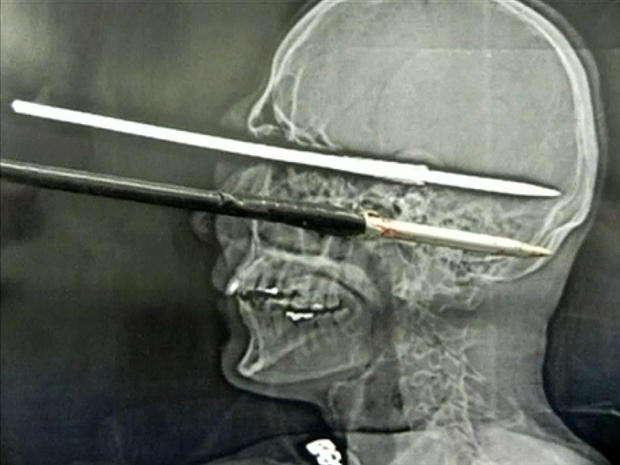

16-year-old Yasser Lopez of Miami was injured when a spear gun his friend was holding accidentally discharged, causing a spear more than three-feet long to impale his skull and brain. Amazingly the teen survived, and was even able to speak to doctors throughout the whole ordeal.